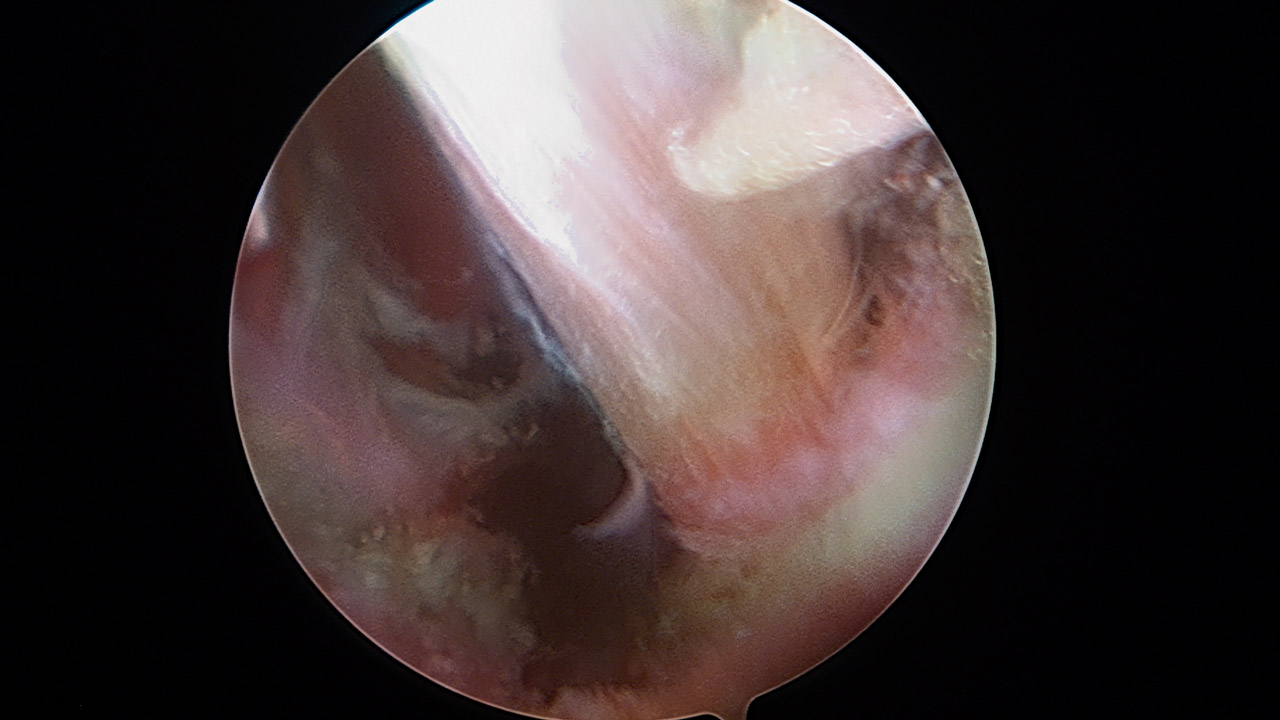

Paso 2: túnel humeral

Cambiamos la visión al portal anterior E, buscando la cara anterior humeral. La posición del brazo se mantiene neutra, sin tracción. Realizamos un portal inferior J con visión directa, que servirá para realizar el túnel humeral. Se diseca el espacio entre la porción larga del bíceps (PLB), el pectoral mayor y el dorsal ancho (Figura 5). Se debe tener precaución con el nervio radial que discurre sobre el dorsal ancho. El punto isométrico de fijación de la plastia se encuentra 1 cm medial a la corredera bicipital y craneal al dorsal ancho. En este punto hay que tener precaución con las “tres hermanas” en la cara inferior del subescapular, ya que el punto de fijación es inferior a las mismas, entre el subescapular y el dorsal ancho . Apoyada en una guía de anclaje Iconix® 2,3, introducimos una aguja de Beath con dirección superior hacia el ángulo posterior del acromion, evitando la posible lesión del nervio axilar en el cuello humeral (Figuras 6 y 7). Se perfora la cortical humeral con un grosor de 7 mm hasta 25 mm de profundidad y se deja una sutura que servirá de transporte del injerto.